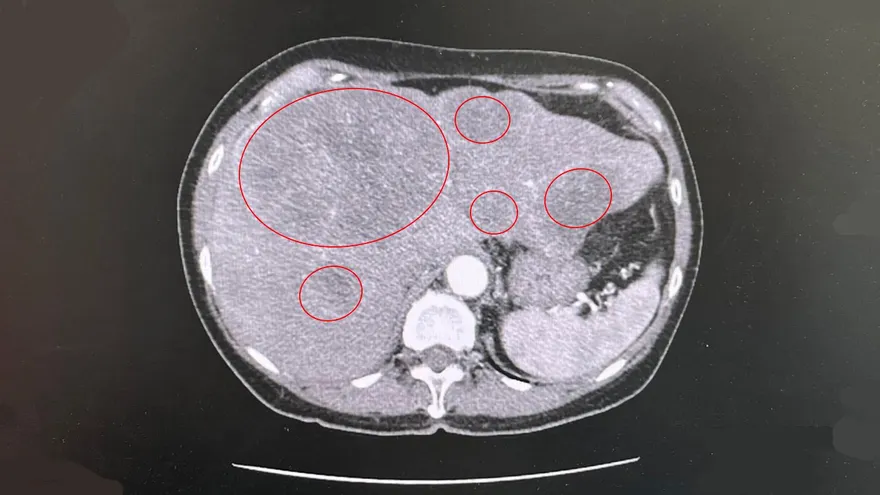

胰臟癌

CA19-9 腫瘤標記